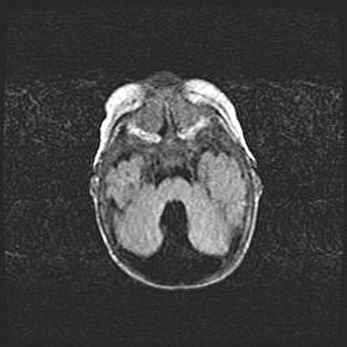

Лейкомаляция с кистозно-глиозной дегенерацией головного мозга.

Возраст: 2 месяца 25 дней

Вес: 6400 г

Окружность головы: 40 см

Срок гестации: 41 неделя

Лейкомаляцию относят к ишемически-гипоксическим повреждениям головного мозга, диагностируемым у новорожденных. При лейкомаляции в головном мозге обнаруживают очаги некроза, возникшие после тяжелой гипоксии и нарушения кровотока. В процессе морфогенеза очаги проходят три стадии: 1) развития некроза, 2) резорбции и 3) формирования глиозного рубца или кисты. Перивентрикулярная лейкомаляция (ПЛ) встречается примерно в 12% случаев среди новорожденных, обычно – у недоношенных детей, причем, частота ее зависит от массы, с которой младенец появился на свет. Наибольшее число малышей страдает лейкомаляцией, если масса при рождении 1500-2500 г.